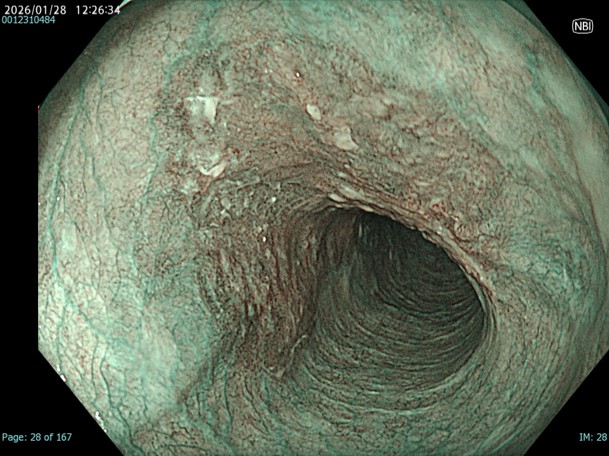

• NBI観察(中遠景)

強調設定:A8

図12

NBI-mode。胸部中部食道に全周性で境界明瞭なBrownish areaを認めます。

• NBI+TXI観察(中遠景)

切替前 NBI強調設定:A8

NBI+TXIレベル:高

図15

NBI+TXI-mode。TXIをかけ合わせる事で中遠景でのDLが明瞭になり、病変が全体として浅い陥凹である事もより視認しやすくなります。